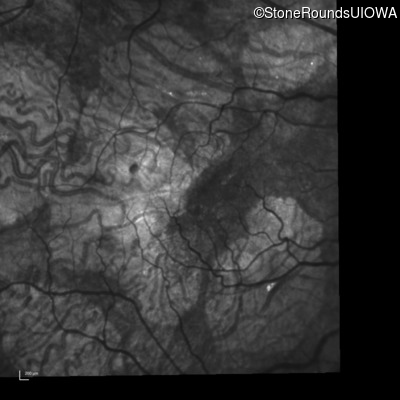

Infrared Fundus Photograph - Left - 20/40 +2

Exemplar